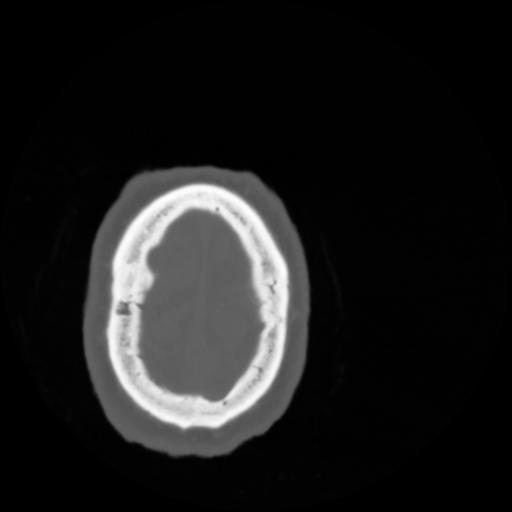

4 CEREBRO,,Vol,0.5,CEREBRO,,